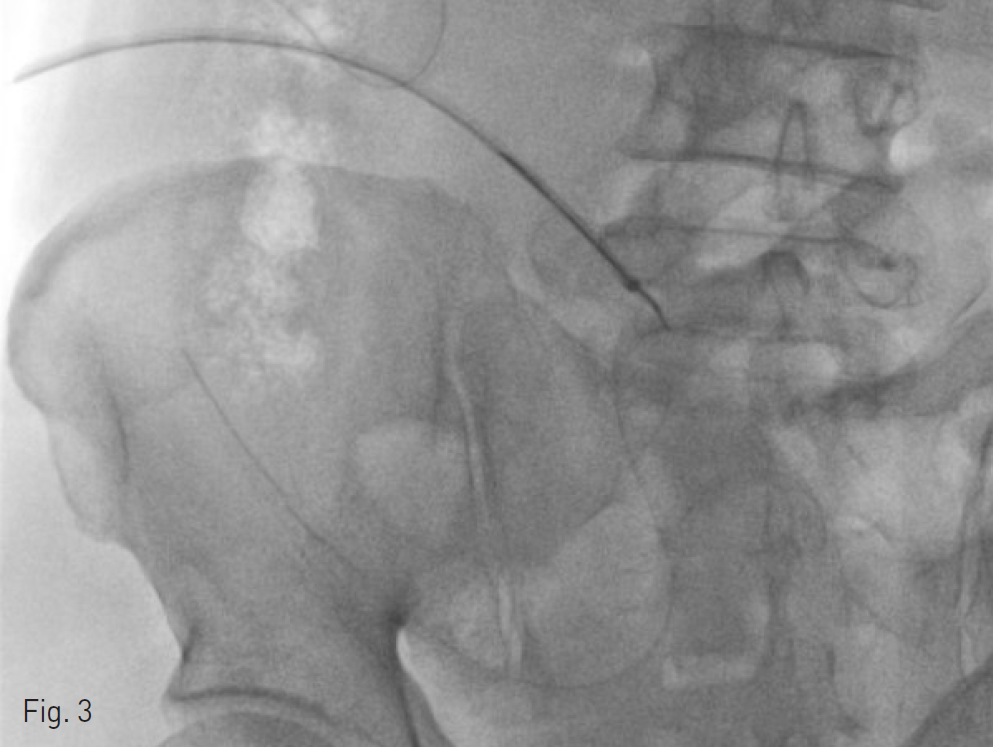

Fig. 3. When retrieving Jackson Pratt drain tube, small bowel was pulled along.

배액관이 삽입되었었던 우하복부위로 0.035-inch guide wire(Radiofocus, Terumo, Tokyo, Japan)와 5-Fr catheter(KMP, Cook, Blomington, USA)를 이용하여 골반강 내로 진입한 후 8-Fr sheath(Flexor check-flo introducer, Cook, Bloomington, USA)를 삽입하였다. 이를 통하여 snare(Amplatz goose neck snare, ev3, Plymouth, USA)를 삽입하였고, 수 차례 시도 후에 잘려진 배액관의 좌측 끝을 잡는 데에 성공하였다. 이후 snare로 잡은 배액관을 당겨서 제거하려고 하였으나 이 과정에서 bowel도 같이 당겨지는 소견을 보여서 bowel이나 mesentery 등이 snare에 같이 잡힌 것은 아닌지 확인하기 위해 cone-beam CT를 다시 한 번 시행하었다. Cone-beam CT 상 이러한 소견은 명확하지는 않았으나, fluoroscopy 소견을 고려하였을 때 bowel이나 mesentery 등이 snare에 같이 잡혀있을 가능성이 있었기 때문에 추가적으로 snare를 삽입하여 반대측으로 접근하여 안전하게 제거하는 것을 시도하였다. 우하복부의 sheath 삽입 부위를 통해 추가적으로 0.035-inch guide wire와 5-Fr catheter를 삽입하고 snare를 이용하여 배액관의 우측 끝을 잡으려고 시도했지만 실패하였다. 이에 다시 앞서 8-Fr sheath를 통하여 넣은, 배액관의 좌측 끝을 잡고 있던 snare를 몇 차례 풀면서 배액관을 당겨 더 이상 bowel이 같이 당겨지지 않는 것을 확인하고 배액관을 몸 밖으로 안전하게 제거하였다.